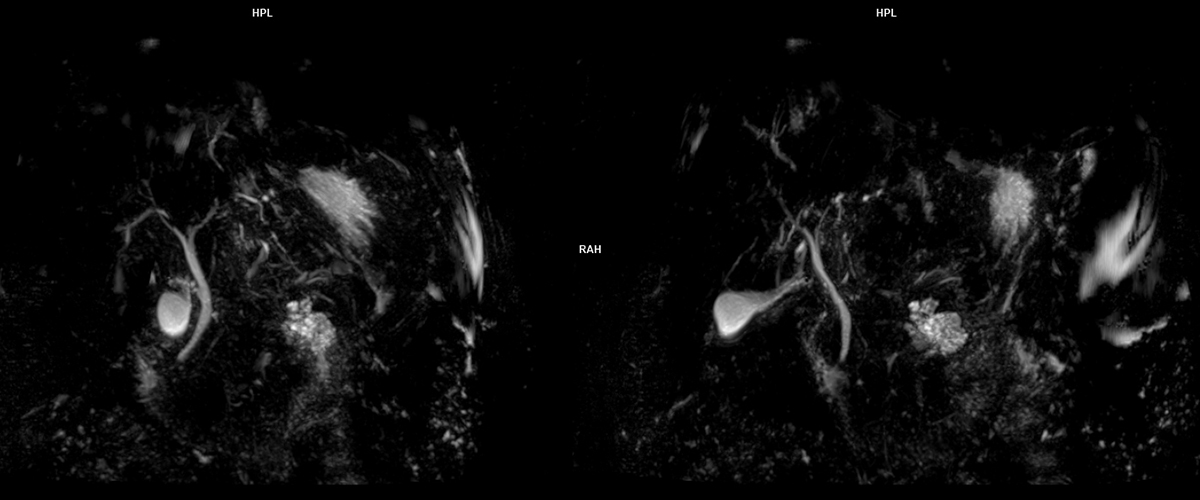

MRCP, safra yolları ve pankreas kanallarıyla ilgili sorunları değerlendirmek için kullanılır:

• Yüksek Çözünürlük: Safra yolları ve pankreas kanalları hakkında detaylı bilgi sunar.